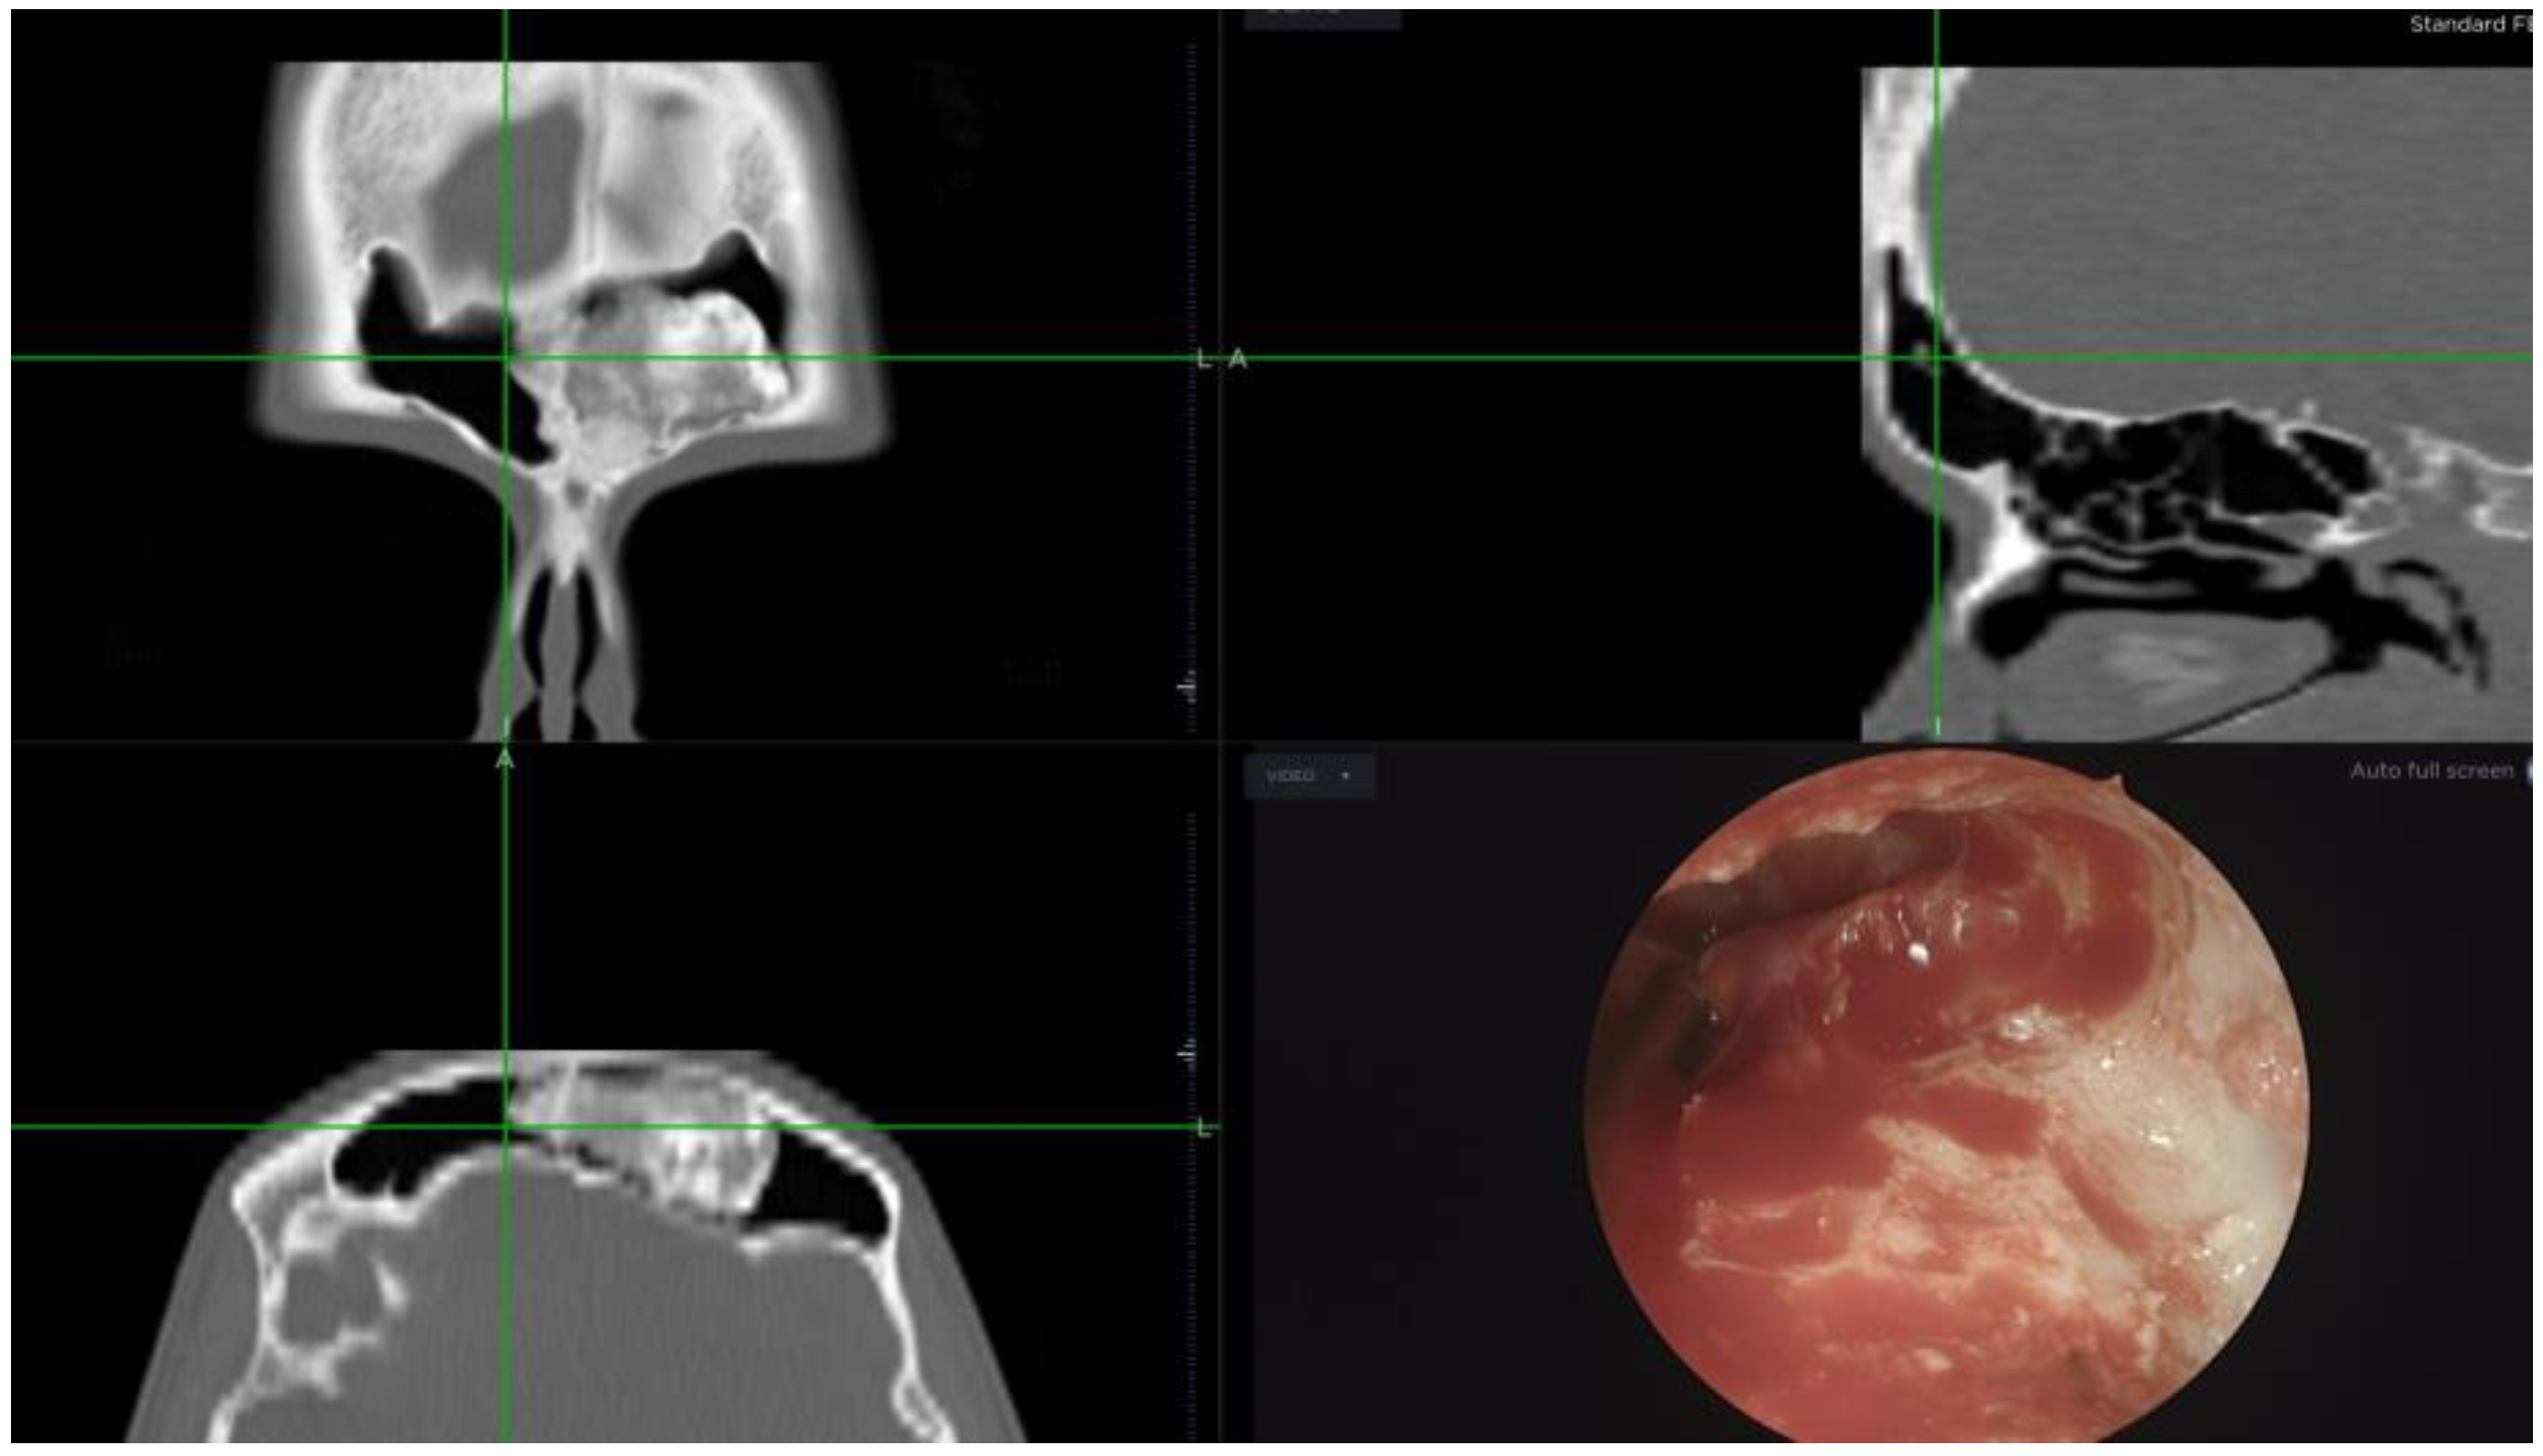

Figure 2. Intraoperative navigation image captured during a Draf III procedure aimed at frontal osteoma removal. Observe the extensive drilling necessary to access the lateral aspect of the lesion.

Another notable finding we observed was the high rate of neo-ostium closure in benign SNT. The vast majority of benign SNT cases in our cohort were osteomas—fourteen osteomas located in the frontal sinus, necessitating extensive drilling during surgery. It is well established, as noted by Rajapaksa et al. [19], that excessive drilling can contribute to restenosis (Figure 2 and Figure 3). Consequently, we hypothesize that this excessive drilling may account for the observed stenosis in this particular subgroup. The use of concurrent flaps and drug-eluding devices may offer a way to reduce neo-ostium stenosis in the future in such patients, and we are currently investigating this.